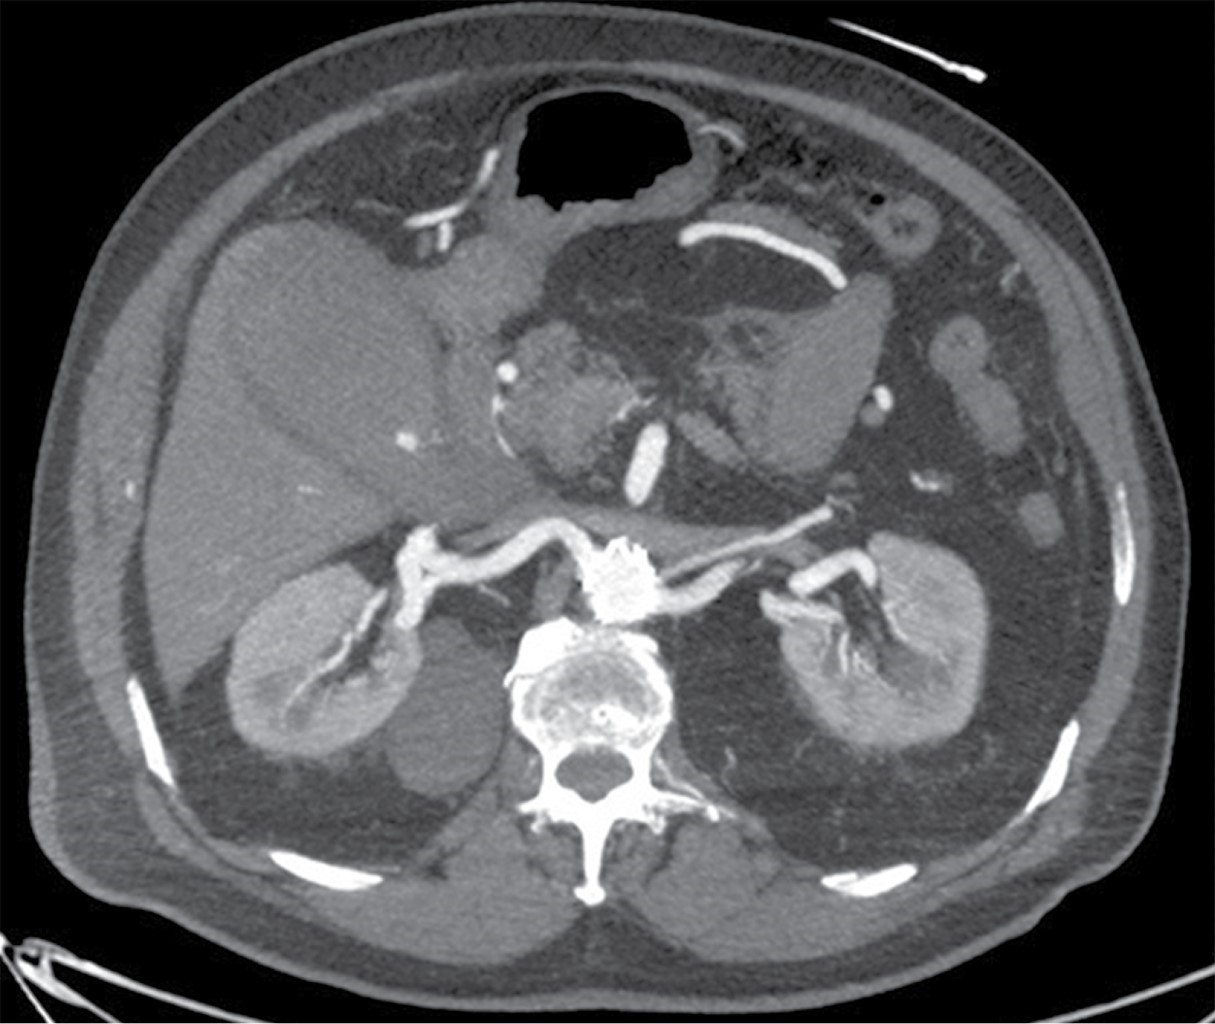

Paciente masculino de 77 años de edad con el antecedente de cardiopatía isquémica no especificada en 2001, tratada con la colocación de dos stents coronarios en acompañamiento con ácido acetilsalicílico; además de tromboembolia pulmonar en 2009, en tratamiento con acenocumarol; y aneurisma aórtico tratado en 2012 con stent aortoiliaco. Acudió a urgencias por presentar dolor abdominal difuso con 12 horas de evolución e intensidad 8/10 en escala de EVA, sin irradiaciones, sin exacerbantes, con náusea sin vómito, se automedicó con butilhioscina y presentó mejoría parcial de 6/10 en escala de EVA. A la exploración física se encontró Glasgow de 15, saturación a 90%, hipertensión arterial 211/116, temperatura de 36 oC, frecuencia respiratoria 13 y abdomen globoso con datos de irritación peritoneal. Los laboratorios reportaron hemoglobina 18.5 g/dl (14.5-18.5), hematocrito 54.4% (42.0-50.0), leucocitos 13.9 103/μl (4.8-10.0), plaquetas 170 103/μl (150-450), TP 42.34 segundos (9.60-12.00), INR 4.33 (0.90-1.20) y TTPa 34 segundos (22-35). Por los antecedentes médicos y quirúrgicos, se decidió realizar angiotomografía computarizada, que reportó sangrado activo hacia la luz de la vesícula biliar (Figuras 1 y 2), hemoperitoneo, stent aortoiliaco permeable y en situación normal, y arteria mesentérica inferior obliterada. Se decidió su ingreso a Terapia Intensiva para estabilización hemodinámica, se transfundieron seis Octapro® (factores de la coagulación IX, II, VII y X), dos paquetes globulares, cuatro plasmas y tres aféresis plaquetarias, además se realizó colecistectomía laparoscópica dos horas después de su ingreso hospitalario.

Los hallazgos ecográficos de colecistitis hemorrágica pueden mostrar engrosamiento de la pared de la vesícula biliar, membranas intraluminales y material ecogénico intraluminal no móvil, ni ensombrecido. Los hallazgos de la tomografía computarizada (TC) pueden demostrar extravasación de contraste, alta atenuación dentro de la luz de la vesícula biliar y estratificación fluido-fluido.10

La TC con fase arterial puede ayudar a diagnosticar y demostrar los hallazgos característicos del engrosamiento de la pared, de la vesícula biliar distendida y los materiales heterogéneos en su interior, además de la extravasación activa del contraste en el lumen de la vesícula biliar.11

Figura 1